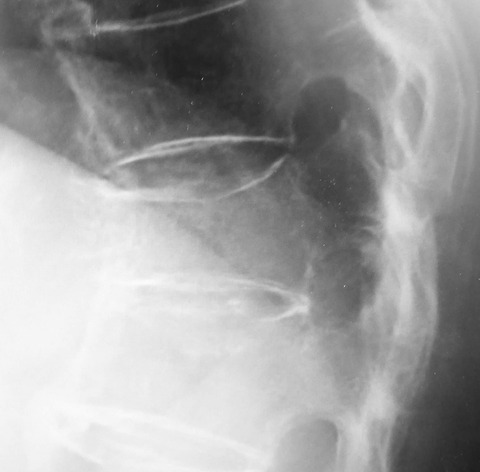

円背のために腹腔容積が減少します。腹腔容積が減少すると、腹圧が高まって逆流性食道炎を併発し、膀胱内圧が高まるために失禁を併発します。

一方、腹腔容積が減少することで胃の容積も減少するため、今回の症例のように以前と比べてお腹が膨れて食事量が落ちるということも併発します。

もちろん、食道や消化管の通過障害の存在を除外診断する必要はありますが、そのような障害が存在しない場合には、円背のために食事の摂取量が落ちたことになります。